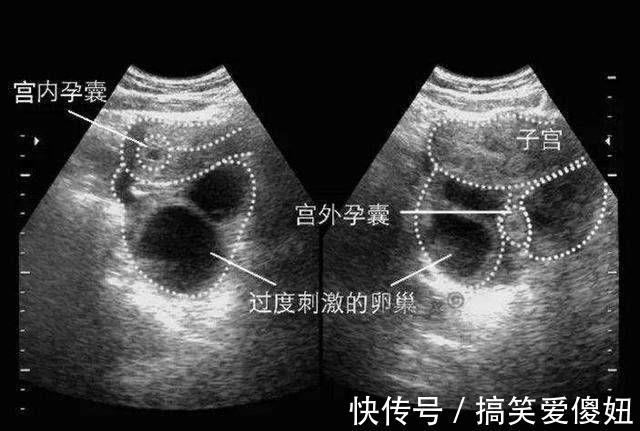

大家都知道,精子和卵细胞结合之后,受精卵正常是要在女人的子宫内着床的。但是,有的时候受精卵却没有进入子宫,而是在子宫外着床了,这种情况就是宫外孕。并且,以在输卵管着床的状况最多。

怀孕对于女人来说是件幸福的事情,但是假如得了宫外孕,那可就悲催了。一般来说,宫外孕的发生很可能是因为输卵管的或者周围有炎症,导致受精卵无法在输卵管中正常通行,导致其在输卵管内滞留并且发育,而产生宫外孕的。检查的时候会发现有腹腔内积血,B超可以作为辅助治疗的手段。